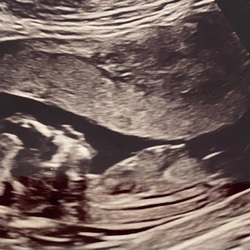

Ik kan ook blijven eten! Vet/pittig eten heb ik wel last van, maar als ik honger heb tussendoor neem ik fruit en VEEL. De kleine man doet het er goed op 😂